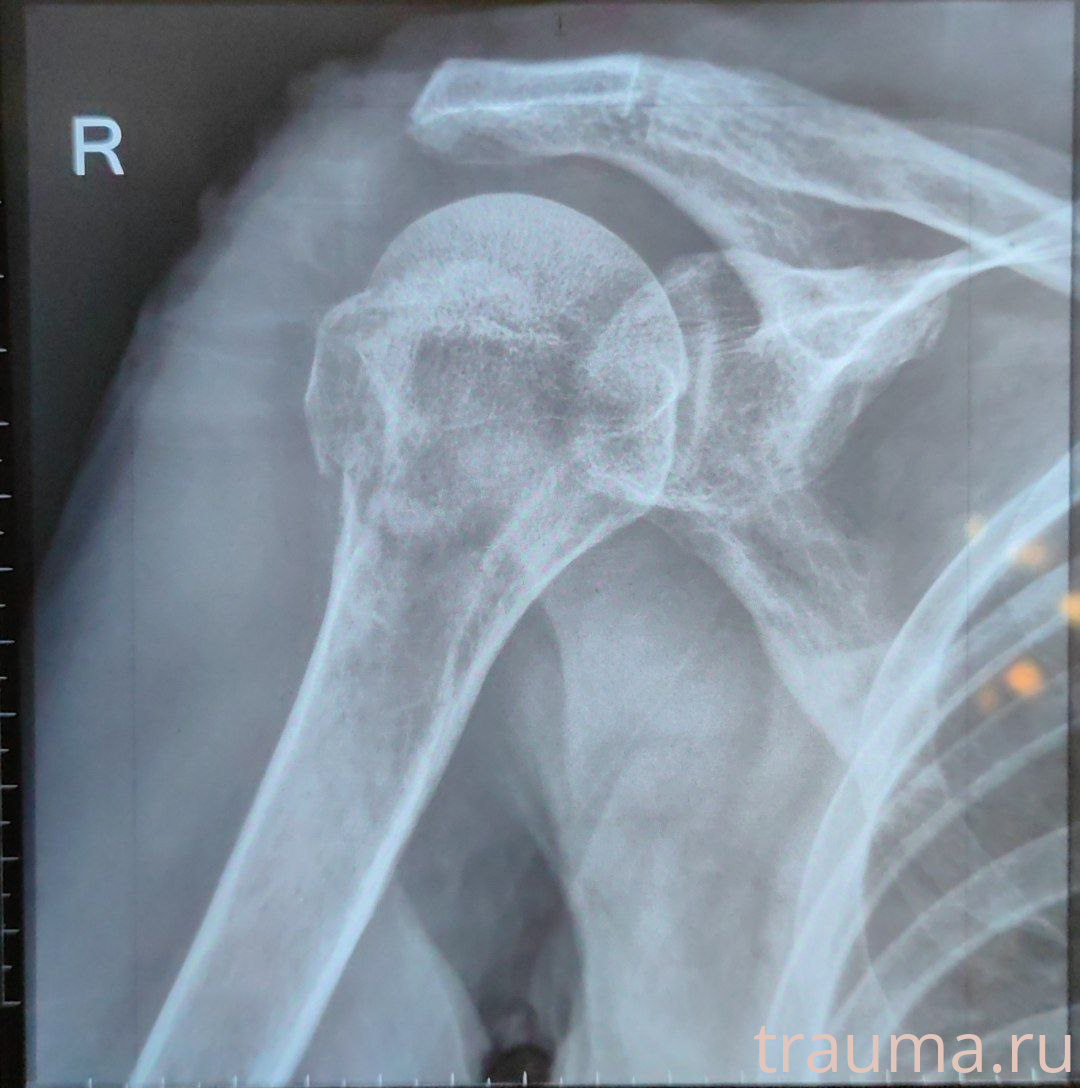

Рентгенограммы

Рентген на дому: по вашему адресу приезжает врач-рентгенолог, травматолог-ортопед с мобильным рентгеновским аппаратом, проводит диагностику травмы или заболевания, делает необходимые рентгенограммы, дает рекомендации по дальнейшему лечению. Получить качественные снимки в домашних условиях возможно благодаря уникальной методике, разработанной МосРентген Центром для института  Склифосовского